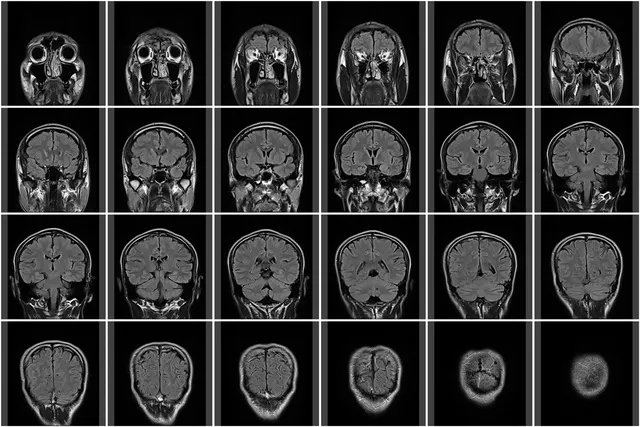

二次性頭痛とは、前述の通り、脳の病気(くも膜下出血、脳梗塞、脳出血、脳腫瘍、髄膜炎など)が原因で起こる頭痛です。

【疑われる病気】 くも膜下出血

・ 脳の動脈瘤(こぶ)が破裂し、脳の表面に出血する病気です。

・ 致死率が非常に高く、発症したらすぐに治療が必要です。

【疑われる病気】 脳卒中(脳梗塞、脳出血)、脳腫瘍

・ 脳の血管が詰まったり(梗塞)、破れたり(出血)しています。

・ 一刻も早く治療を開始しないと、命に関わったり、重い後遺症が残ったりします。

【疑われる病気】 髄膜炎(ずいまくえん)、脳炎

・ 脳や脊髄を覆う「髄膜」に、細菌やウイルスが感染して炎症を起こしています。

・ これも緊急治療が必要な、非常に危険な病気です。

【疑われる病気】 脳腫瘍、慢性硬膜下血腫(まんせいこうまくかけっしゅ)

・ 脳の中に「できもの(腫瘍)」ができたり、じわじわと出血が溜まったりして、脳を圧迫している可能性があります。